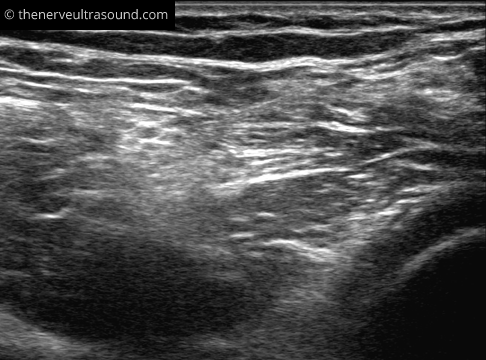

The sciatic nerve lies quite superficial at the subgluteal region and the popliteal fossa. In between the nerve runs deeper and might be difficult to identify clearly in obese patients. Starting the scanning more distally at the position E in the knee fold makes it easier to identify the nerve at the positions C and D.

The site of the bifurcation of the sciatic nerve into the tibial and common peroneal nerve is variable. Often the portion of the sciatic nerve forming the tibial or the common peroneal nerve can be already identified much more proximal to the bifurcation.